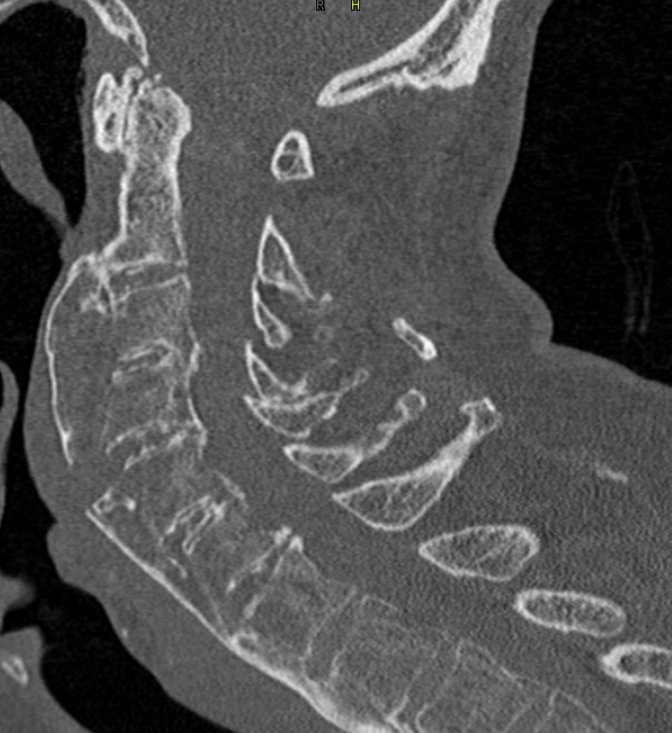

3. Chalkstick fracture of fused cervical spine